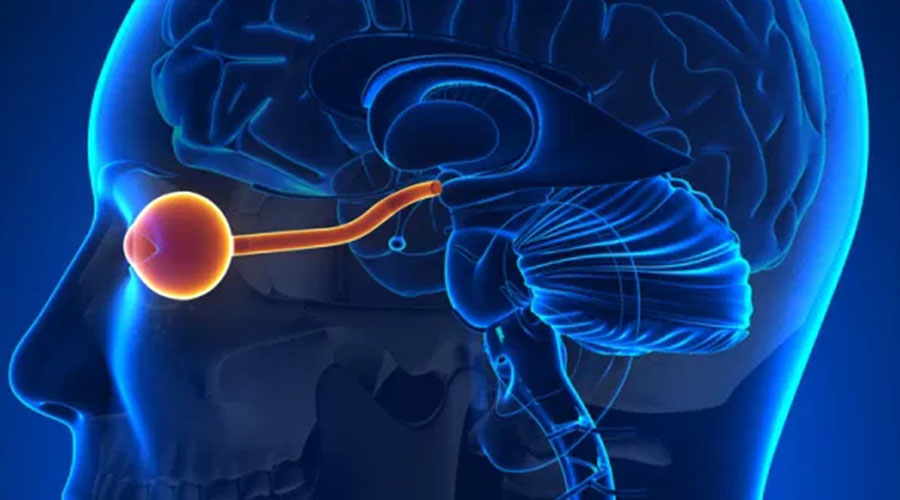

Neuro-ophthalmology is a medical speciality that bridges the neurology and ophthalmology gap, dealing with

problems that involve the brain, optic nerve, and eye movements.

Neuroophthalmology is concerned with disorders of the nervous system related to vision problems, including

disorders affecting the brain, optic nerves, and muscles that control the movement of the eyes. These